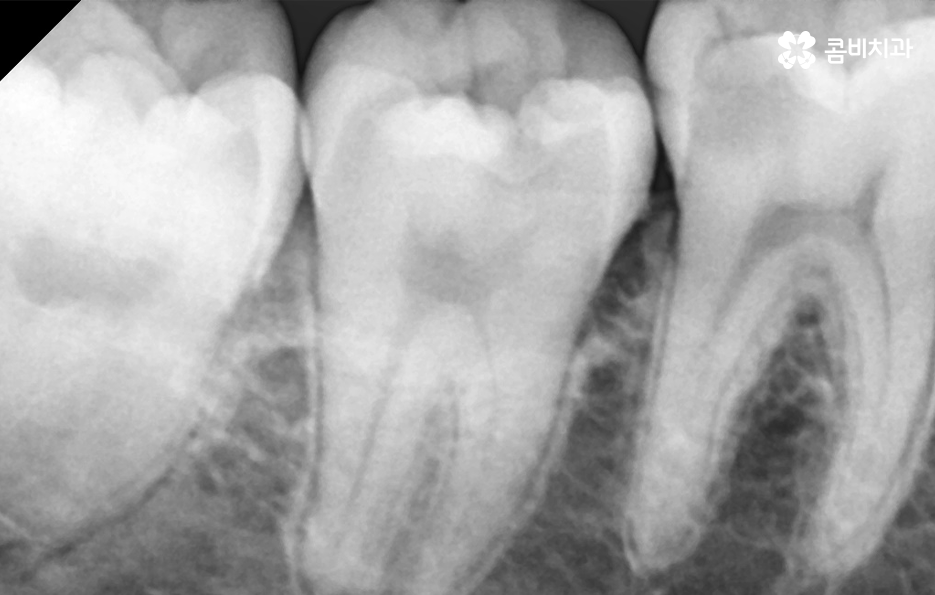

충치는 진행 단계에 따라 법랑질 충치와 상아질 충치, 신경조직의 충치, 뿌리 충치 이렇게 4단계로 구분할 수 있는데요. 쉽게 생각하면 치아의 구조로 볼 때 겉 부분을 이루는 법랑질부터 치아 안쪽으로 충치가 점점 깊어지고 심해지는 단계라고 이해하시면 될 거예요

충치 치료는 이처럼 진행 단계나 충치가 발생한 위치, 깊이 등에 따라 보통 레진, 인레이, 크라운 순서로 치료 방법이 달라지고 있는데요. 그중에서도 충치 신경치료의 경우 통증도 심하고 치료도 여러 진행되며 비용도 비싸다는 인식 때문에 신경치료를 일단 미루고 상태를 지켜보자고 생각하시는 분들도 있어요

충치 신경치료는 언제 하는지 대표적인 사례를 살펴보면 크게 두 가지로 구분할 수 있는데요. 충치가 신경조직에 근접하거나 침범한 경우 진행하는 신경치료가 있고 치아 뿌리 끝에 염증이나 고름 같은 게 생겨서 신경치료를 하는 경우가 있어요